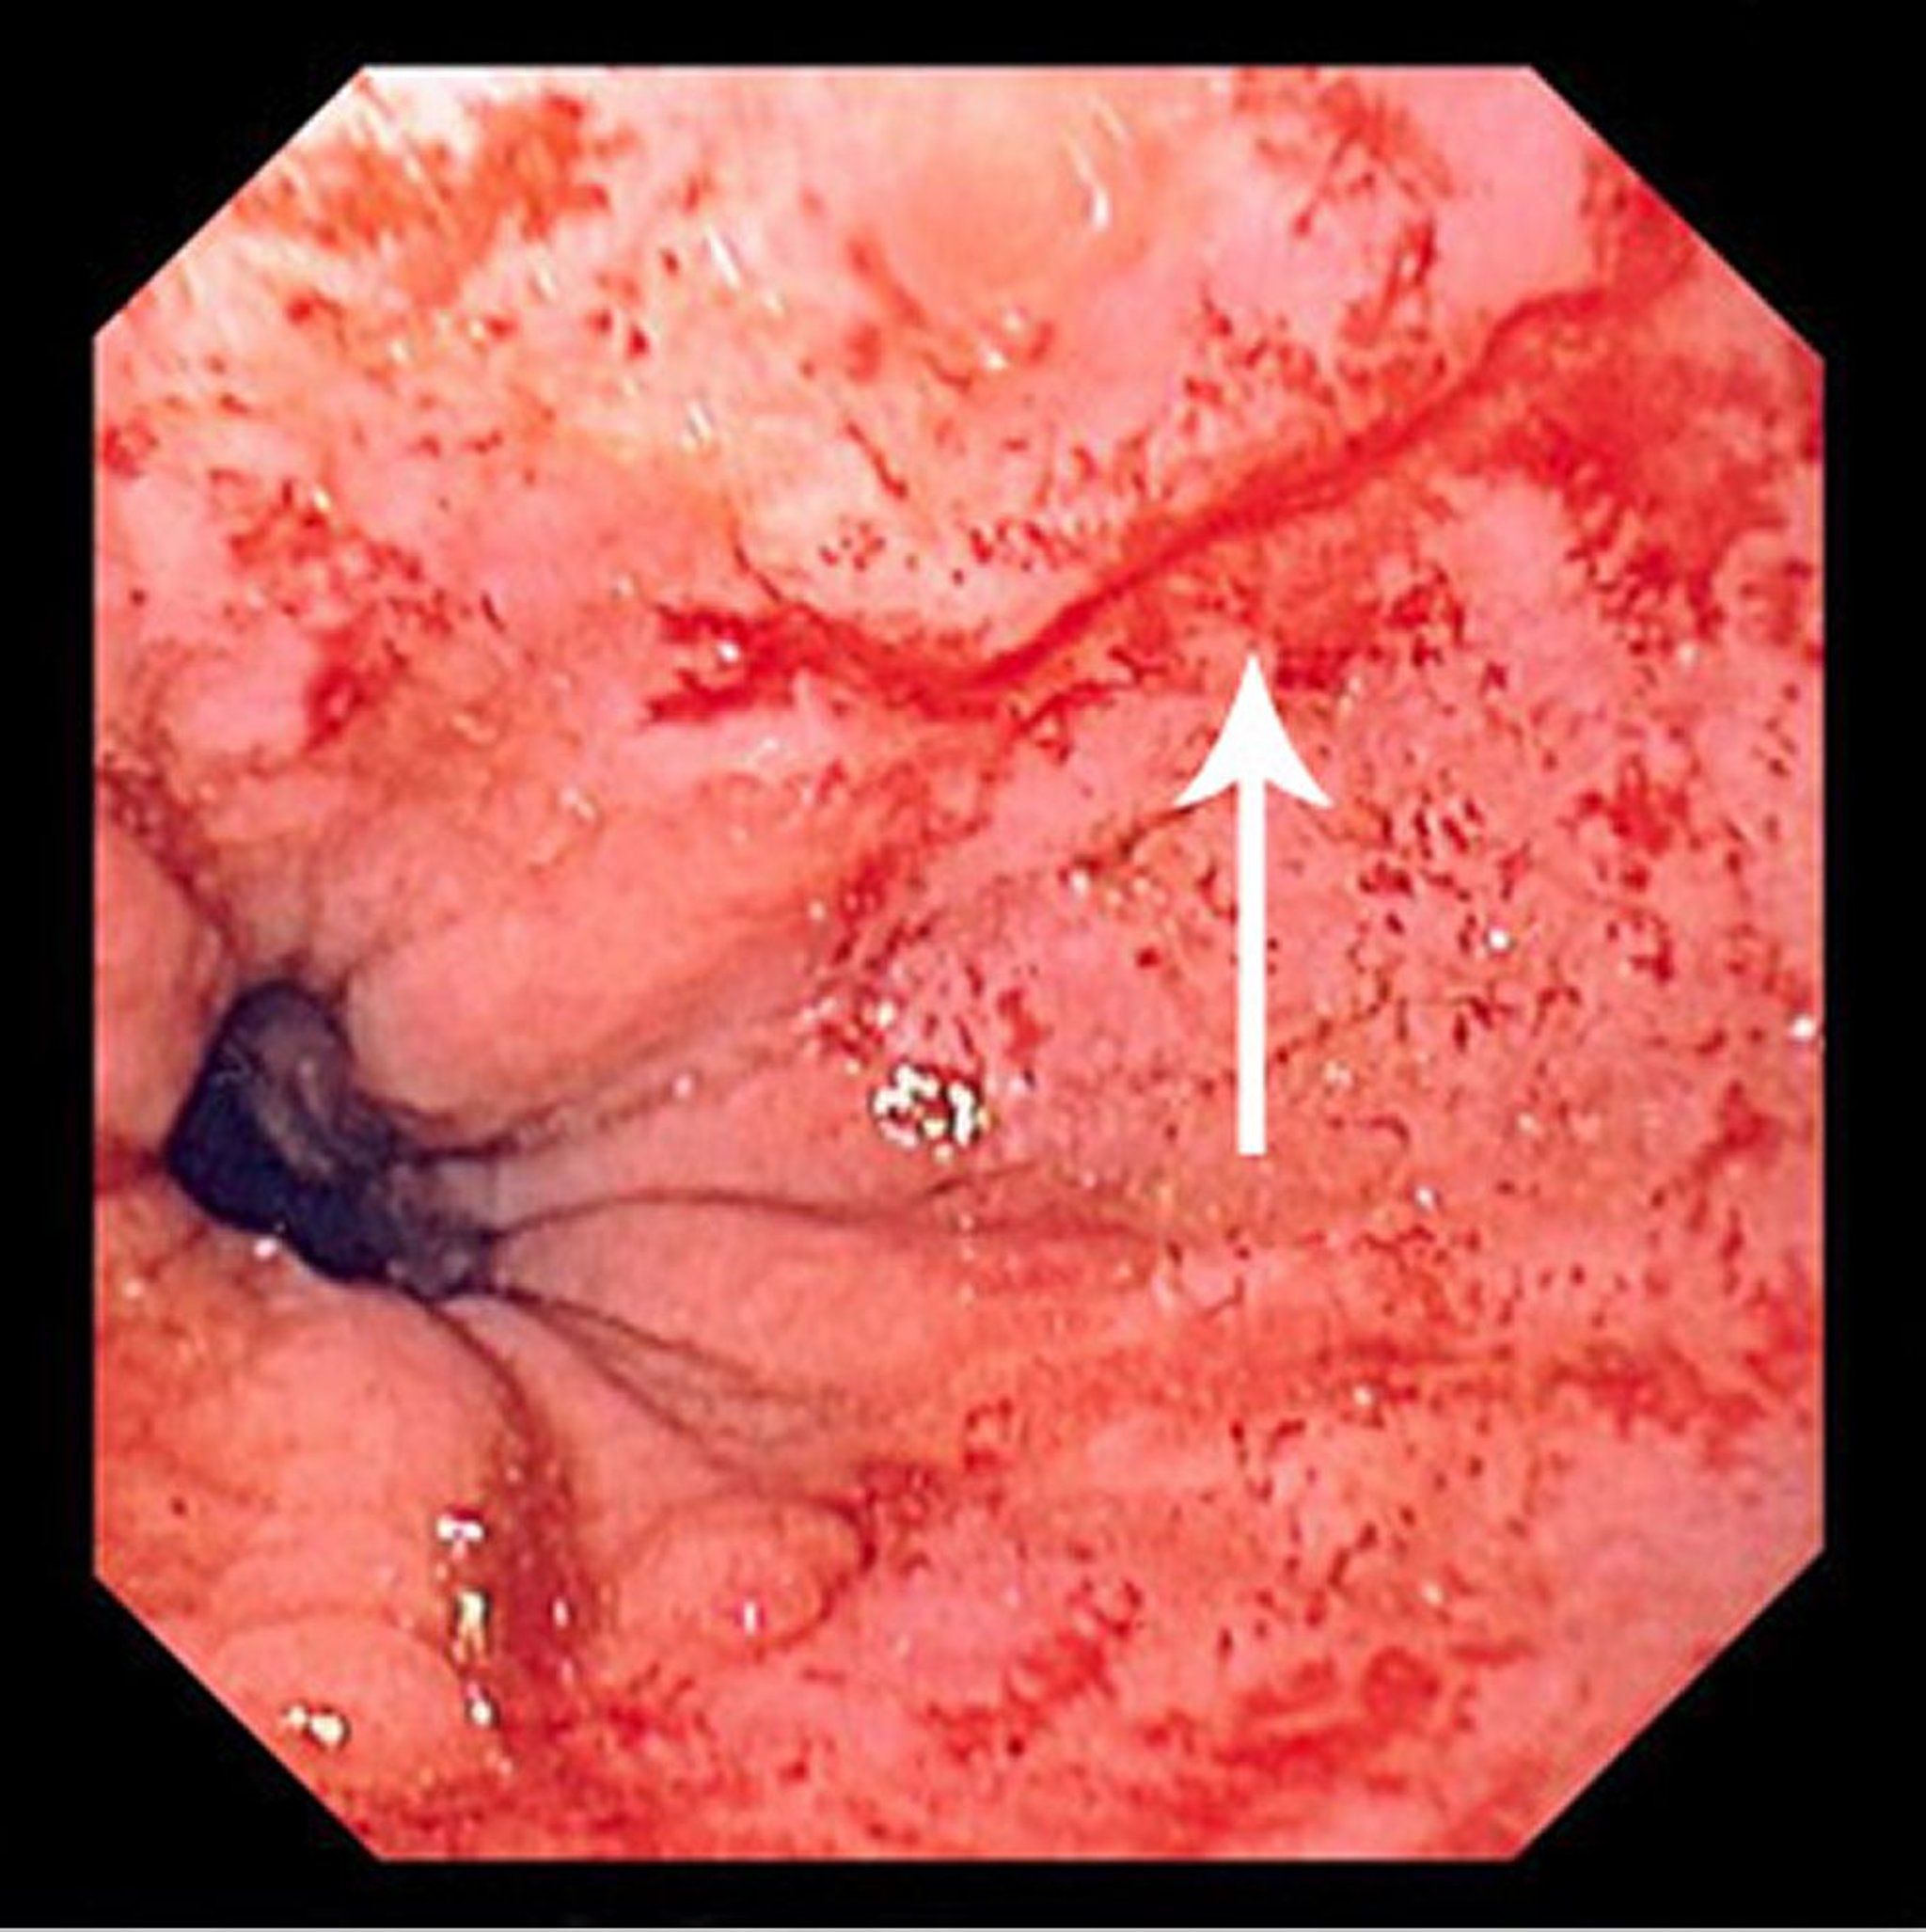

Mallory-Weiss-Riss

Dieses Bild zeigt einen dünnen, linearen Riss (Pfeil), der direkt über der Magenschleimhautgrenze beginnt und sich nach proximal erstreckt.

Image provided by David M. Martin, MD.